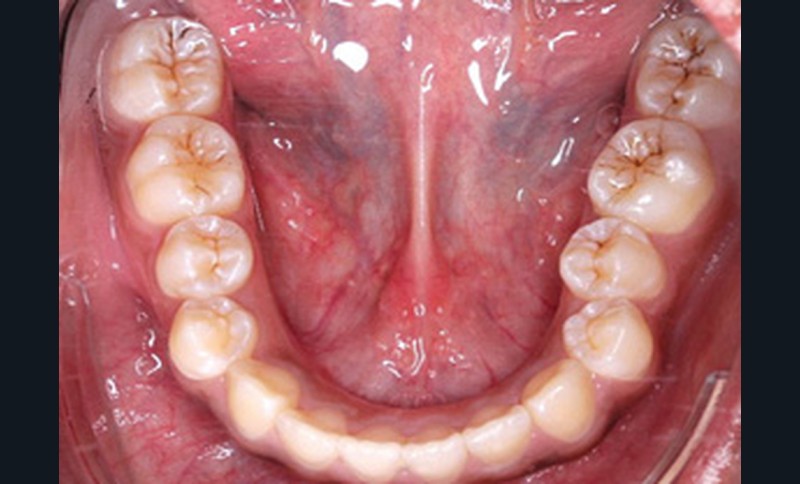

L’examen clinique endo-buccal révèle une denture adulte jeune avec un inversé d’articulé antérieur de 13 à 23, des tatouages gingivaux ethniques et des taches de décalcifications, un parodonte sain mais un brossage insuffisant.

L’arcade maxillaire est en V et la voûte palatine profonde. L’arcade mandibulaire a une forme en U (non-concordance des formes d’arcade) et présente des malpositions des dents cuspidées. La médiane mandibulaire est décalée à gauche de 2 mm ; le recouvrement antérieur est de 2 mm ; les molaires sont en classe III avec un surplomb inversé.